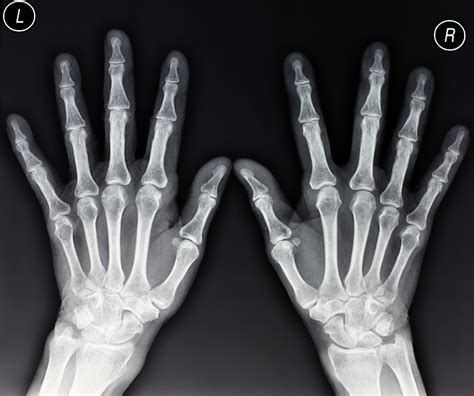

When you experience pain, swelling, or a limited range of motion in your fingers or wrist, your healthcare provider may recommend an X-ray of hand to get a clearer picture of what is happening beneath the skin. This common diagnostic tool is often the first line of defense in identifying bone-related issues, ranging from subtle hairline fractures to the degenerative effects of arthritis. By utilizing small doses of radiation, an X-ray creates detailed images of the intricate internal structures of the hand, providing essential information that is invisible during a standard physical examination.

The human hand is a complex structure comprised of 27 bones, along with numerous joints, tendons, and ligaments. Because of its constant use in daily activities, the hand is highly susceptible to injuries and chronic conditions. An X-ray of hand is requested by physicians to accurately diagnose a variety of clinical presentations. Without this imaging, it would be impossible to distinguish between a soft-tissue injury, such as a sprain, and a structural injury, like a fracture.

The entire process for an X-ray of hand typically takes only a few minutes. You will be guided by an X-ray technologist to a specialized imaging room. You will likely be asked to sit at a table next to the X-ray machine. The technologist will position your hand in several specific angles—usually a posterior-anterior (PA) view, an oblique view, and a lateral view—to ensure they capture a comprehensive perspective of all bones and joints.

Once the images are captured, they are sent to a radiologist—a doctor who specializes in reading diagnostic medical imaging. The radiologist examines the film for signs of damage or disease. They then prepare a formal report and send it to your primary doctor or the specialist who ordered the test. It is essential to remember that you should not attempt to interpret these images yourself; what might appear to be a fracture to an untrained eye could simply be a natural growth plate, a normal anatomical variation, or a shadow.